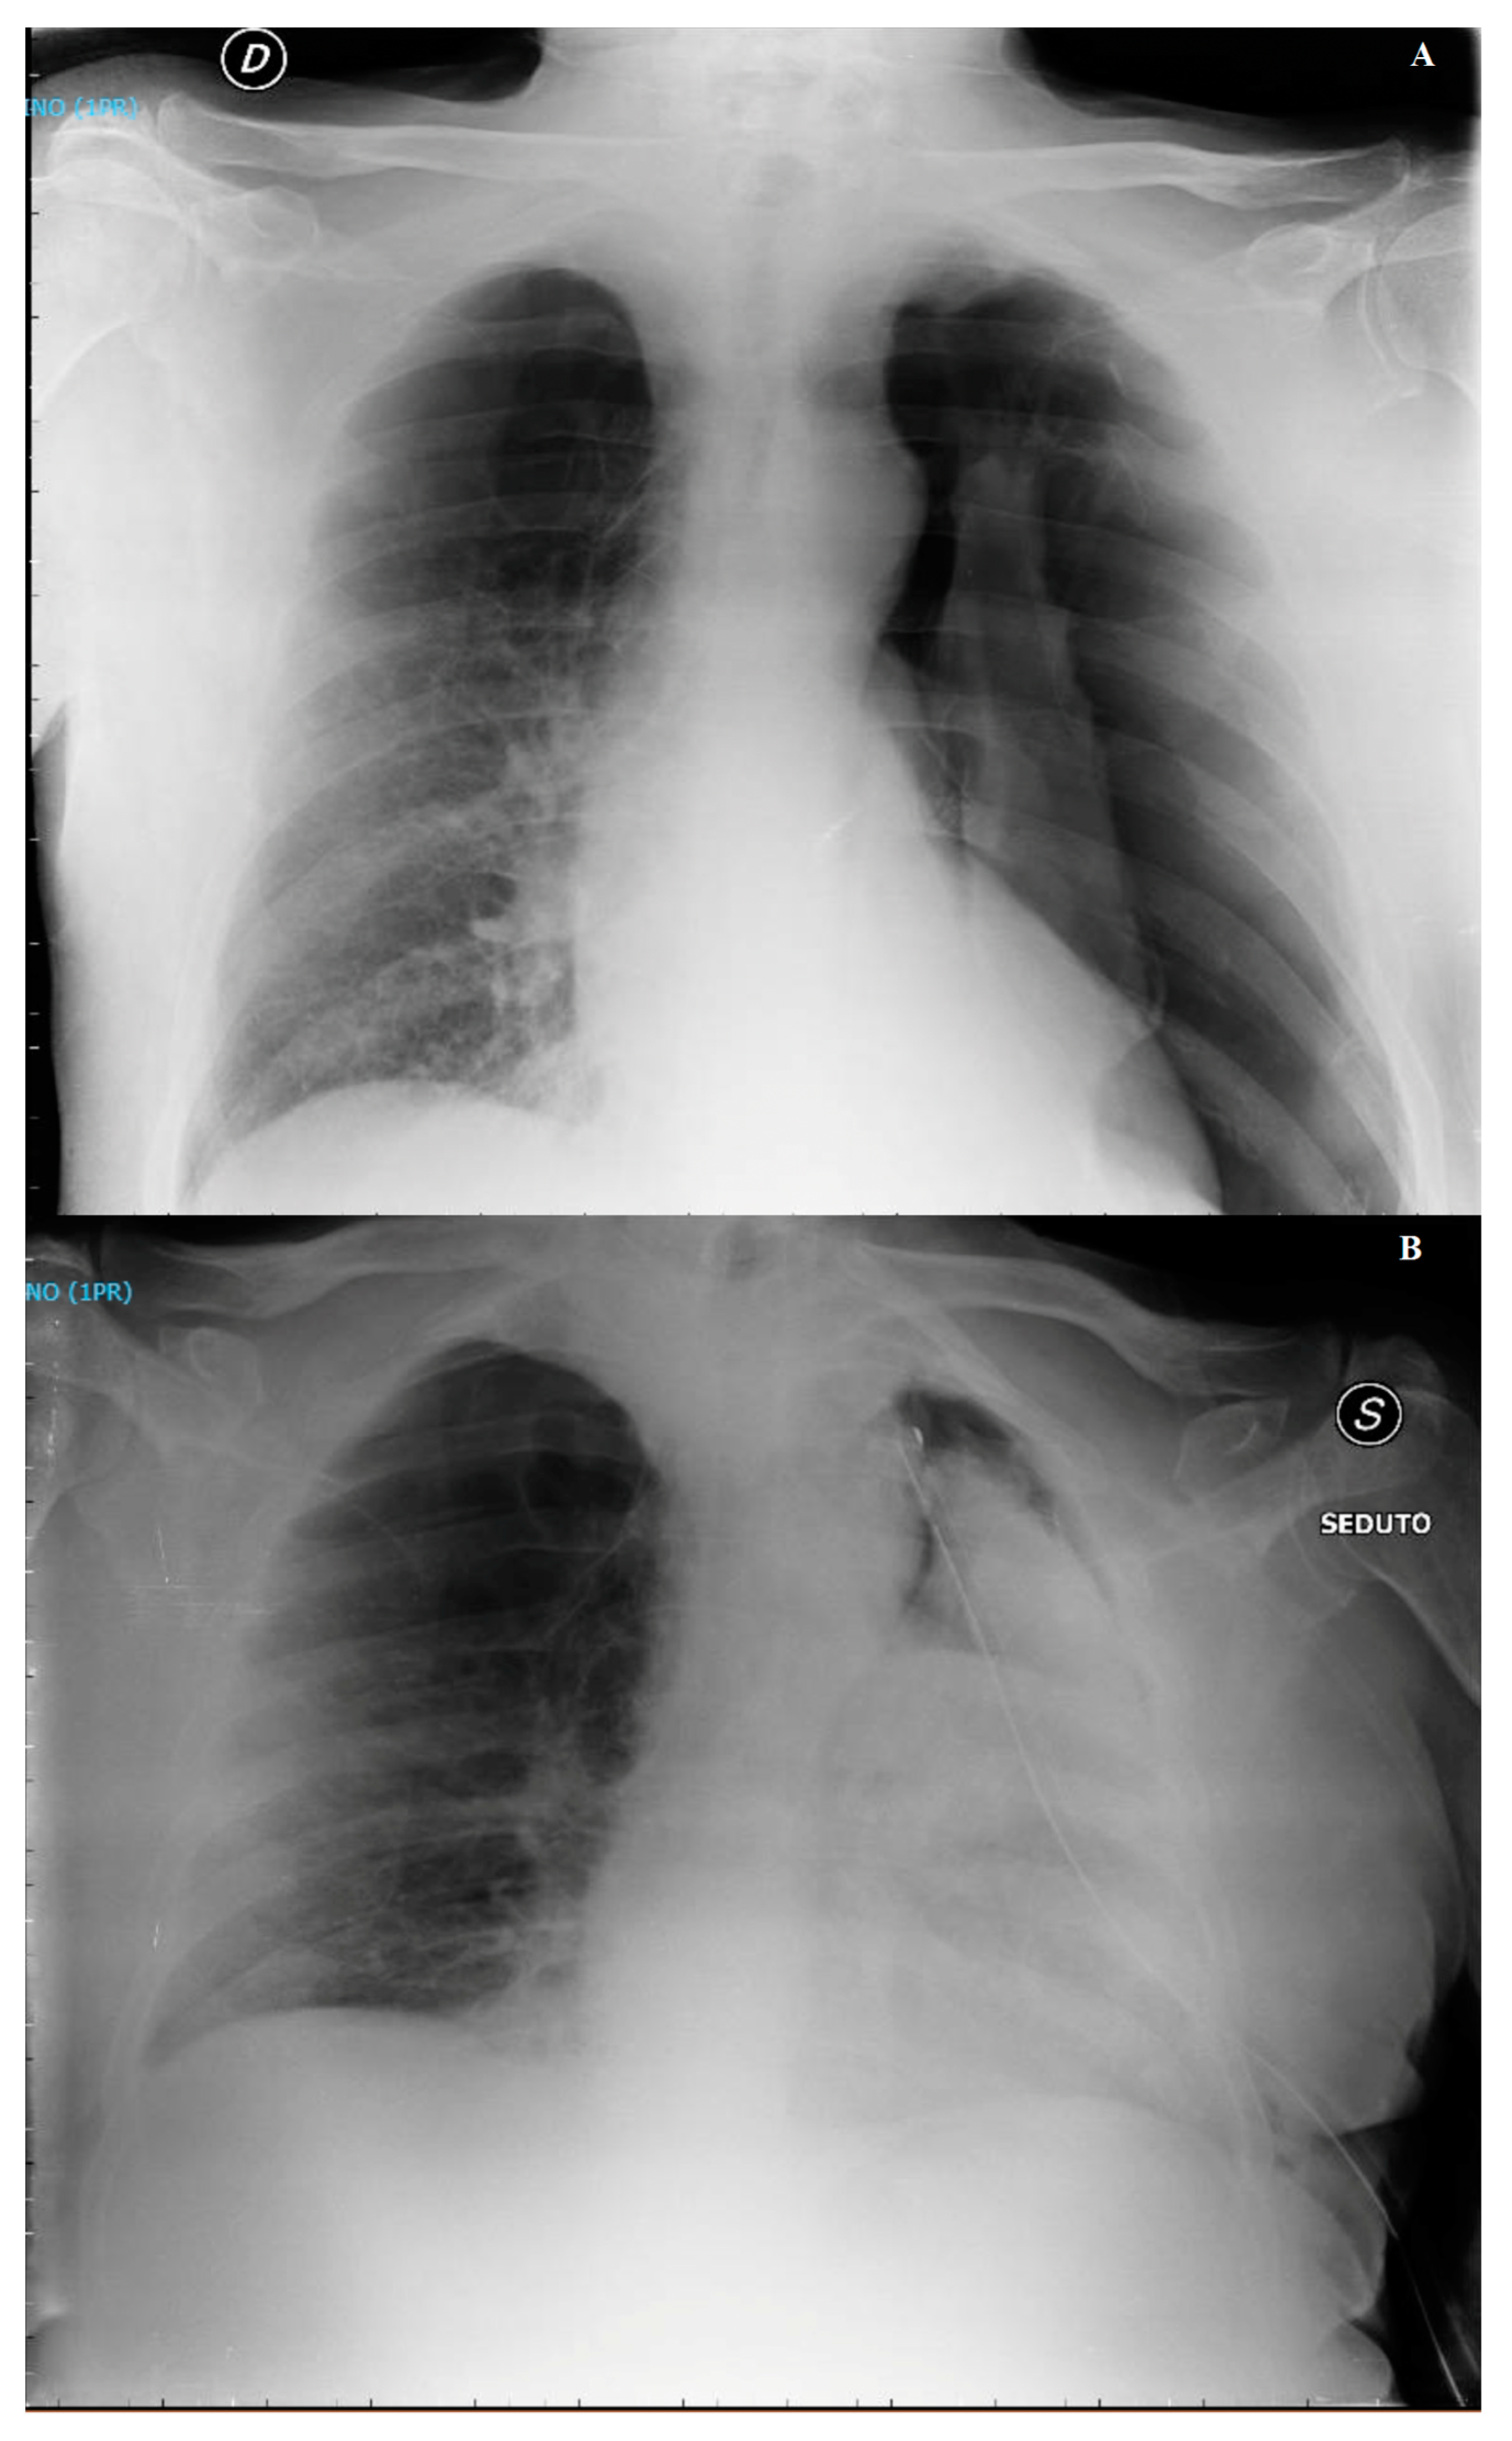

3.1. Case 1

3.2. Case 2

3.3. Case 3

4.3. Clinical and Radiological Features